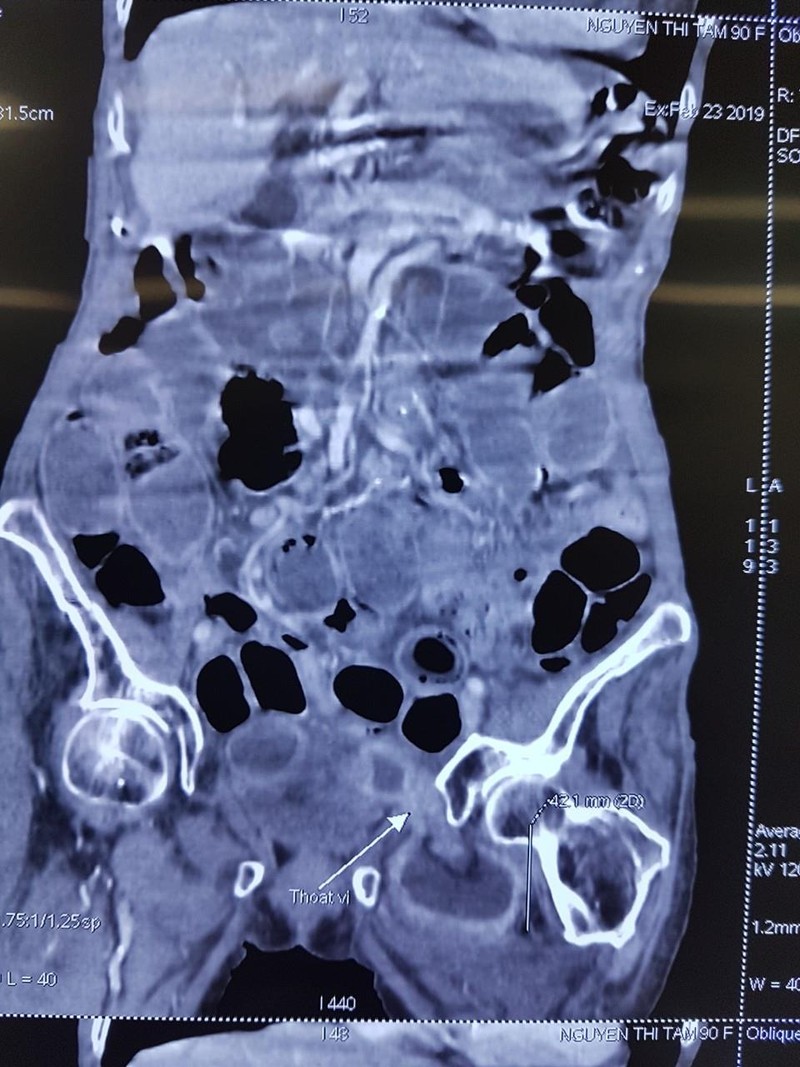

Hình ảnh chụp CT của bệnh nhân

Bệnh nhân lập tức được mổ cấp cứu. Các bác sỹ đã kiểm tra toàn bộ ruột non thấy cách góc hồi manh tràng khoảng 25 – 30cm quai hỗng tràng thoát vị nghẹt vào trong hố bịt. Đúng như chẩn đoán, thành ruột đã bị hoại tử với lỗ thủng có đường kính 2cm, bờ mép nham mở mủn nát, có mủ. Kíp mổ khẩn trương hội chẩn cấp cứu với Chỉ huy Khoa tại bàn mổ ngay trong đêm và quyết định cắt đoạn ruột kèm lỗ thủng, phục hồi lưu thông tiêu hóa. Sau đó, các bác sỹ đã xử lý để tránh tái phát cho bệnh nhân.

Theo BS. Nguyễn Văn Trưởng, thoát vị bịt là bệnh lý hiếm gặp, chiếm khoảng 0,07 – 1%. Bệnh hay xảy ra ở phụ nữ lớn tuổi, gầy, sinh đẻ nhiều như bệnh nhân NTT đã 7 lần sinh. Một phần của quai ruột bị mắc kẹt trong lỗ bịt vì lỗ bịt nhỏ không đủ để toàn bộ chu vi của quai ruột chui vào, thành phần hay gặp đó là đoạn cuối hồi tràng. Triệu chứng của bệnh không điển hình, chẩn đoán sớm thường khó khăn, bệnh diễn biến nhanh dẫn đến hoại tử, thủng ruột trên nền bệnh nhân già, yếu, nhiều bệnh lý kết hợp nên nguy cơ biến chứng nặng và tỷ lệ tử vong cao.